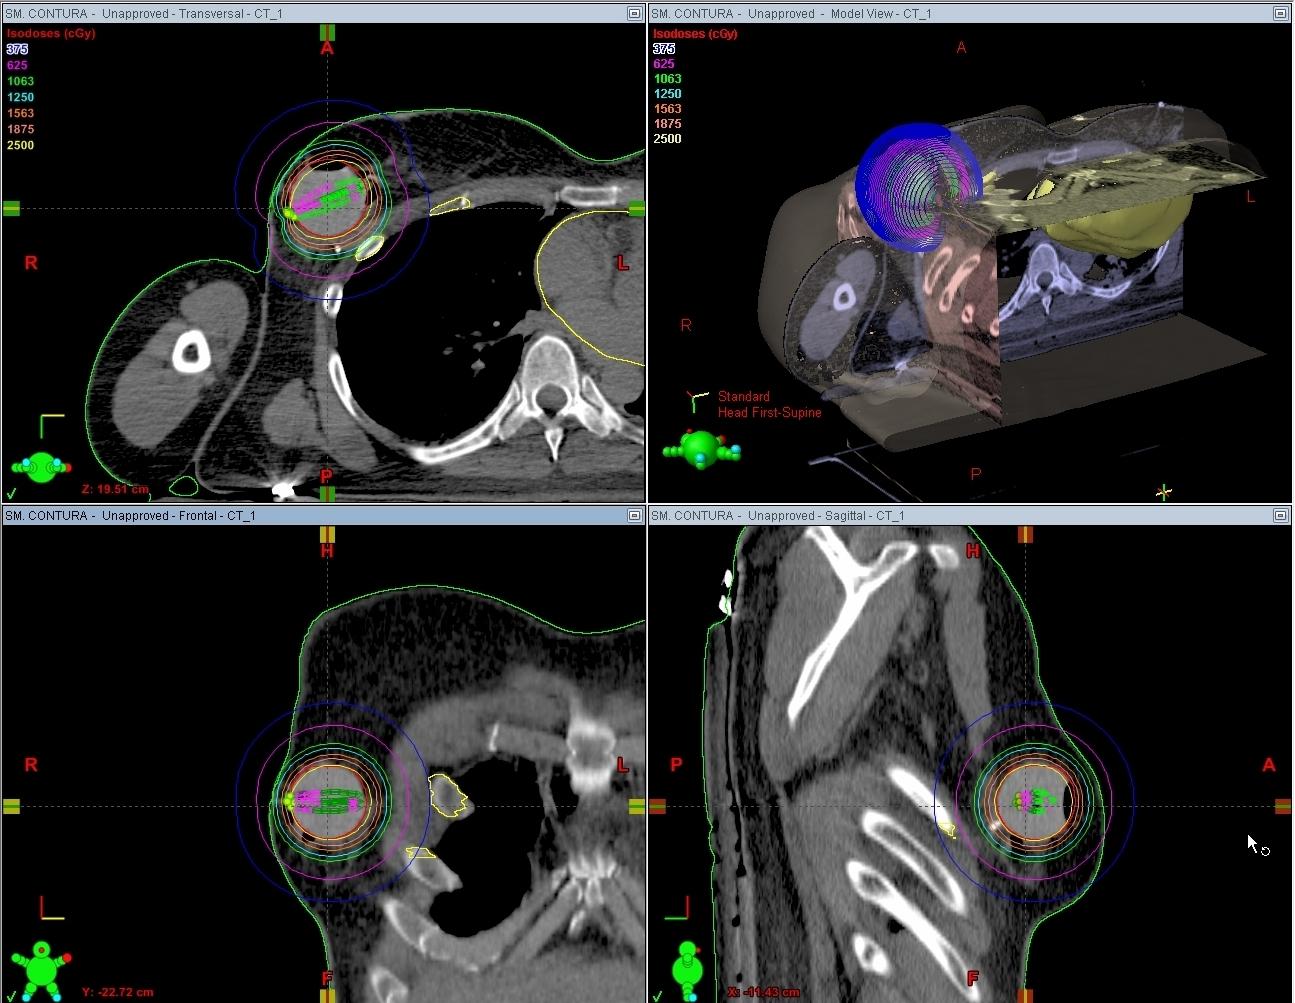

Precision Breast IORT is a unique form of IORT developed at UVA — now being examined in a Phase II clinical trial — that incorporates CT imaging and high-dose rate (HDR) brachytherapy, allowing the breast cancer specialists at UVA to provide an individualized radiation treatment to their patients. When compared to conventional IORT, Precision Breast IORT involves a higher dose of radiation directed to the area of the breast where the tumor was removed, while sculpting the dose away from the breast, lung and skin.